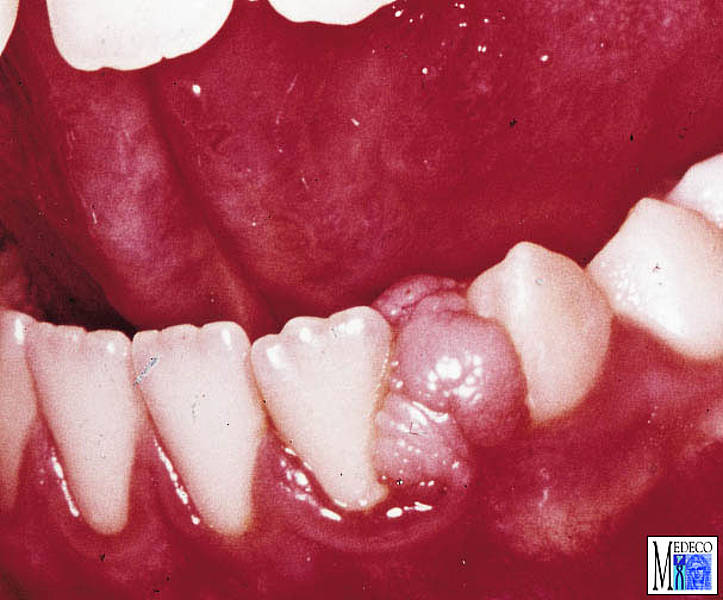

El épulis es tejido que sobresale del periodoncio. La coloración puede

variar entre rosa pálido y rojo oscuro en base al porcentaje de vasos

sanguíneos implicados. La terapia consiste en la eliminación (excisión).

El épulis tiende a ser recidivo. No obstante también pueden desaparecer

de forma espontánea.